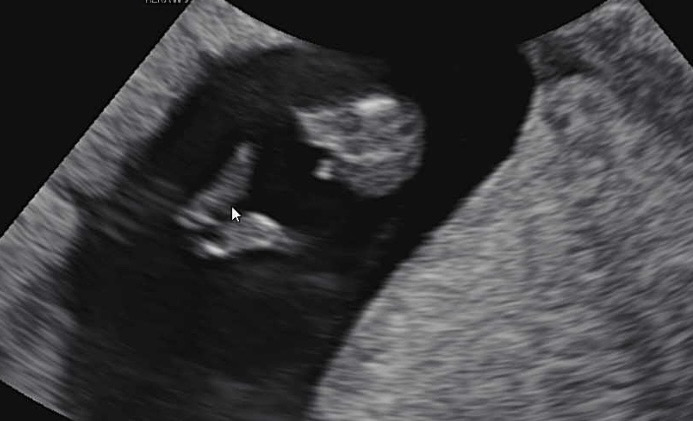

10주4일차 초음파보고왔어요!

아직은 성별모르는거 알고있는데 점세개보이면 남자라그랬는데 첫째도 남아거든욯 여자애들도 이쯤에는 저렇게 보일수도잇나요?ㅋㅋ 아들일거같은 느낌이 확 드네요 입덧도 있고 첫째도있다보니 생각잘안했는데 귀도생기고 손발도생기고 잘크고있는거보니 대견ㅠㅠㅎㅏ네요